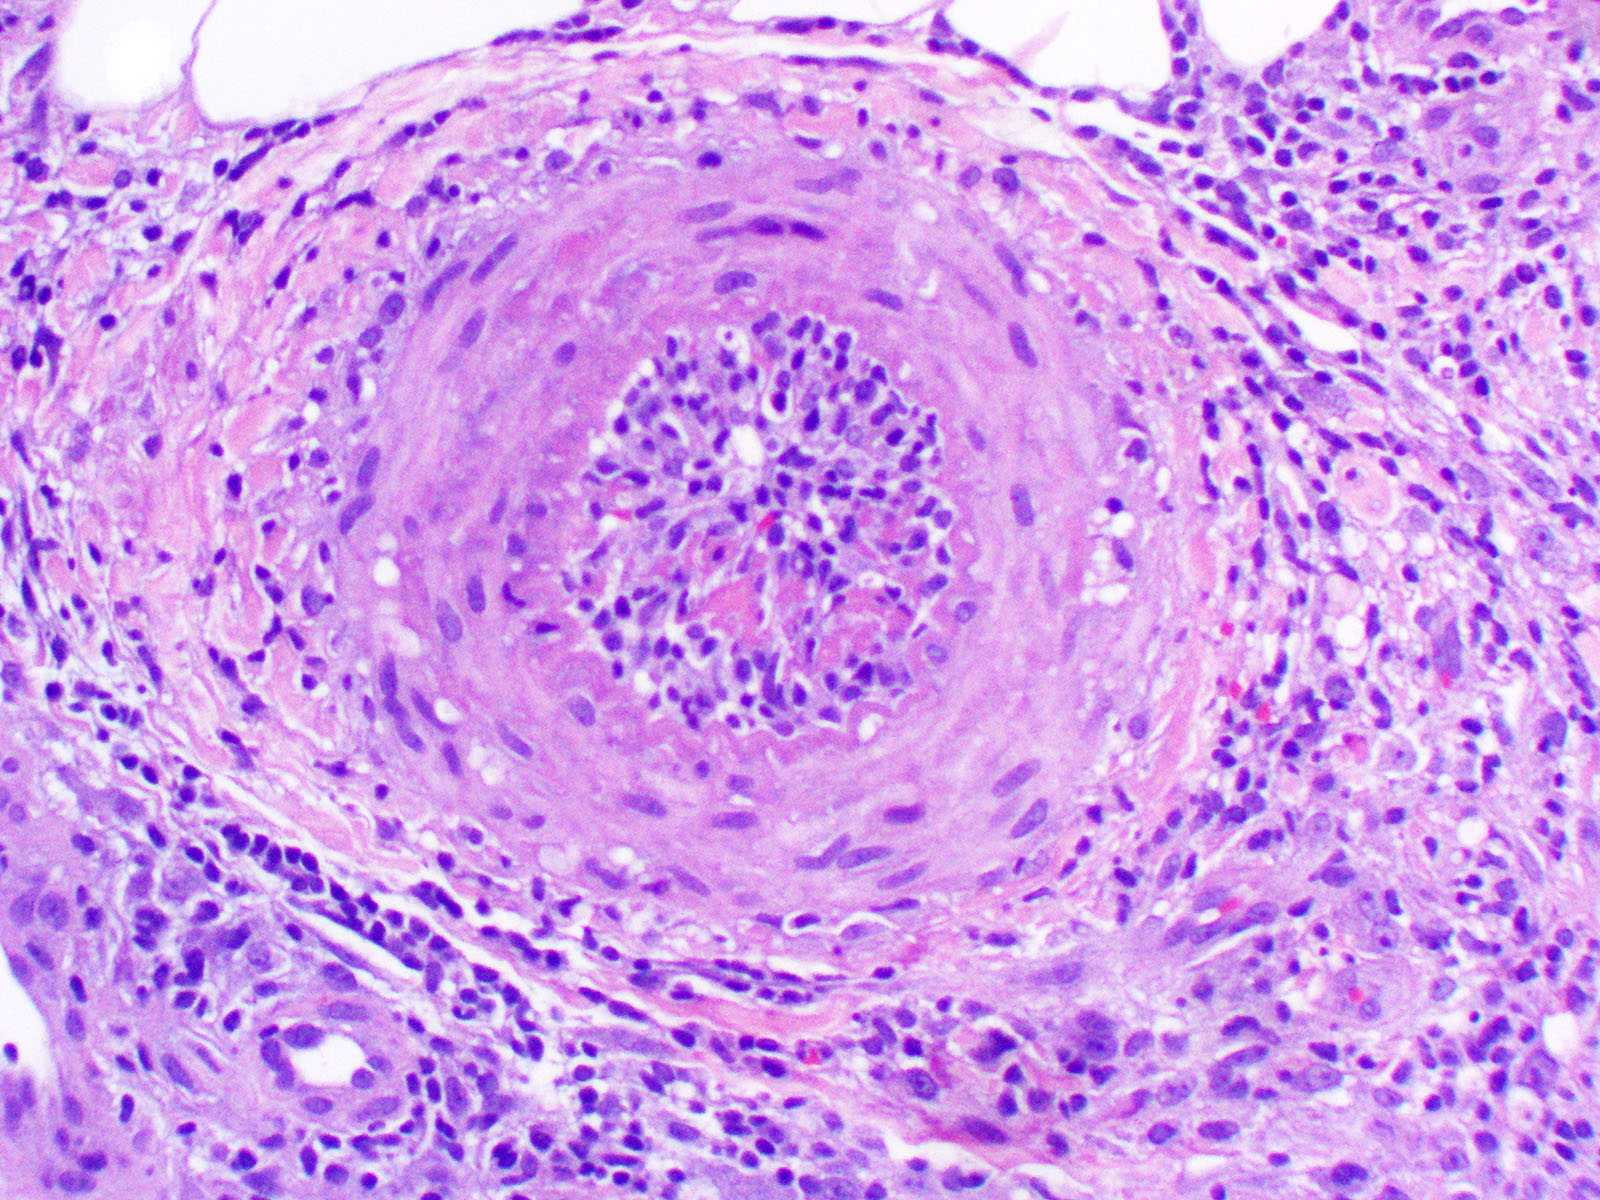

Proinflammatory mechanisms in immune complex vasculitis. Immune Fingertip Vasculitis Vasculitis symptoms include rash, body aches or discomfort, decreased appetite, fatigue, and fever—among others. Fatigue or a general feeling of being sick. Concept of ‘vasculitis as a syndrome’ vasculitis is a syndrome with an array of clinical features as. Vasculitis is the inflammation of blood vessels, leading to decreased blood flow. Kidney problems (including dark pee or blood in your. Fingertip Vasculitis.